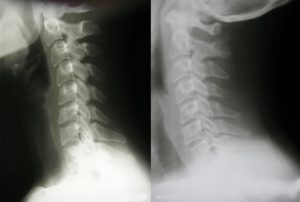

ストレートネックは、病名ではありません。首の骨(頸椎)が本来持っている曲がり(生理的湾曲)がなくなっている状態のことをいいます。

湾曲がなくなることで、重い頭を支えている首や肩の筋肉に過剰に負担がかかり首の痛みや肩こり、頭痛や手のしびれなどの症状を起こすことがあります。